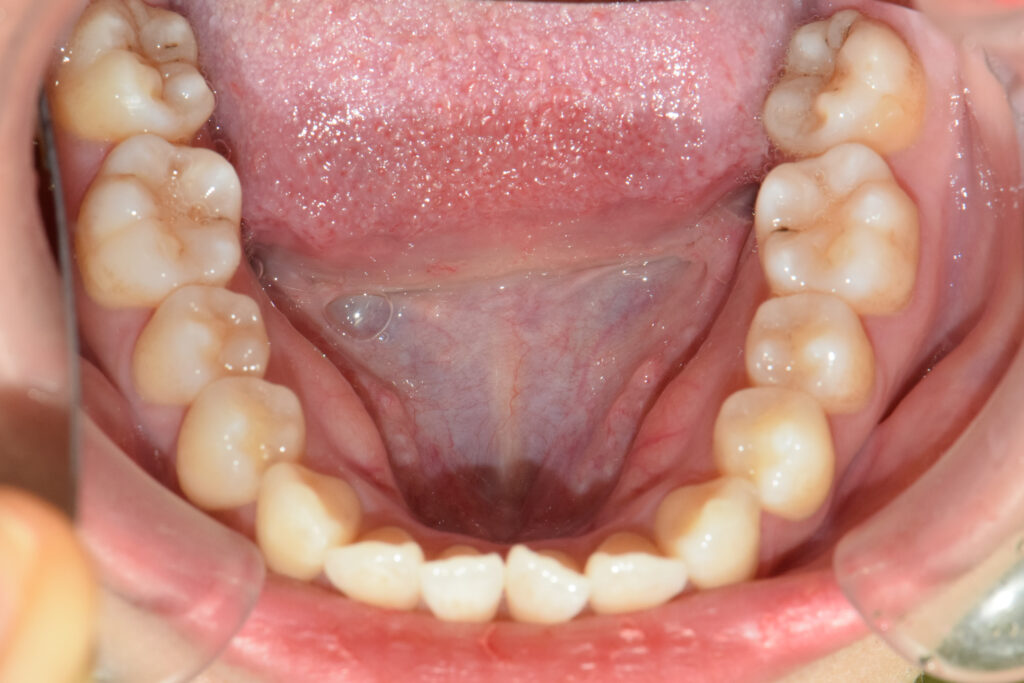

下顎

治療前